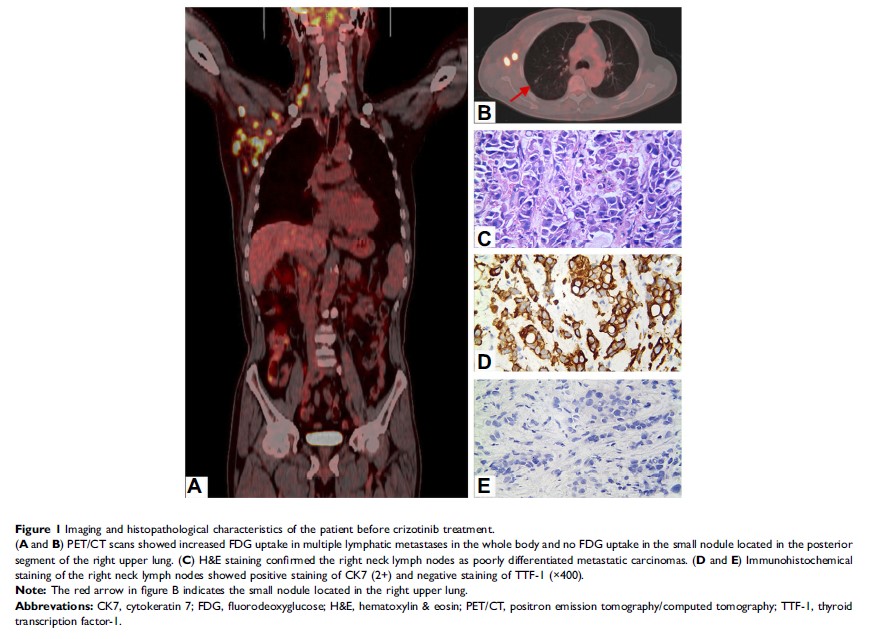

Case Report

克唑替尼治疗 MET 扩增和 NTRK 1 共突变的原发灶不明转移性腺癌并获得完全缓解一例